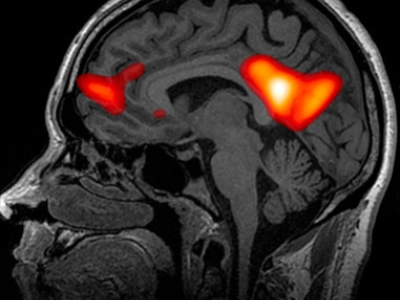

Las propiedades psicodélicas de estas setas provienen de varios compuestos químicos que interactúan principalmente con el sistema serotoninérgico del cerebro. Aquí te presentamos los más importantes:

- Carhart-Harris, R. L., et al. (2012). Neural correlates of the psychedelic state as determined by fMRI studies with psilocybin. Proceedings of the National Academy of Sciences, 109(6), 2138-2143.